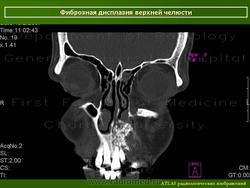

Локализация: для монооссальной фиброзной дисплазии характерно поражение одной из костей лицевого черепа, а также бедренной или большеберцовой кости, реже одного ребра; при полиоссальной фиброзной дисплазии страдают в первую очередь бедренная, большеберцовая и тазовые кости, не исключено и поражение мелких костей стопы, черепа, реже ребер. Рентгенологическая картина фиброзной дисплазии разнообразна. Патологические участки могут быть то более плотными, то более прозрачными по сравнению с окружающей костью, иногда имеют вид «матового стекла». Одни очаги четко отграничены зоной склероза, контуры других расплывчатые, что особенно характерно для костей черепа. Нередко выявляются узуры в кортикальном слое, а при наличии перелома — отчетливая периостальная реакция. При макроскопическом исследовании определяются беловато-красные опухолевые очаги разной плотности, в зависимости от степени выраженности их минерализации. Имеются многочисленные кисты, заполненные желтоватой или красноватой жидкостью, и полупрозрачные участки хряща до 3 см в диаметре.

Для фиброзной остеодисплазии, или болезни Брайцева-Лихтенштейна, характерно нарушение костеобразующей функции мезенхимы, проявляющееся в одной или нескольких костях, что ведет к их деформации и образованию в них очагов разрежения, обычно отграниченных от здоровой ткани кости склеротической каймой. Объем пораженной кости при этом может быть увеличен. Чаще поражаются трубчатые кости, но характерные изменения могут отмечаться и в костях черепа. В таких случаях возможны облитерация придаточных полостей носа, деформация глазниц, сужение отверстий в основании мозгового черепа и в лицевом черепе, ведущее к нарушению функции проходящих через них нервов и сосудов. Заболевание, возможно, наследственное, проявляется с детских лет. Описал в I927 г. отечественный хирург В.Р. Брайцев (1878-1964), несколько позже - американский патологоанатом L. Lichtenstein (1906-1977).